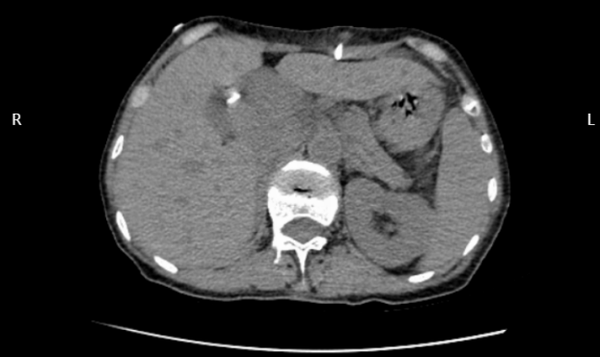

術(shù)前CT和B超顯示肝內(nèi)外膽管擴(kuò)張